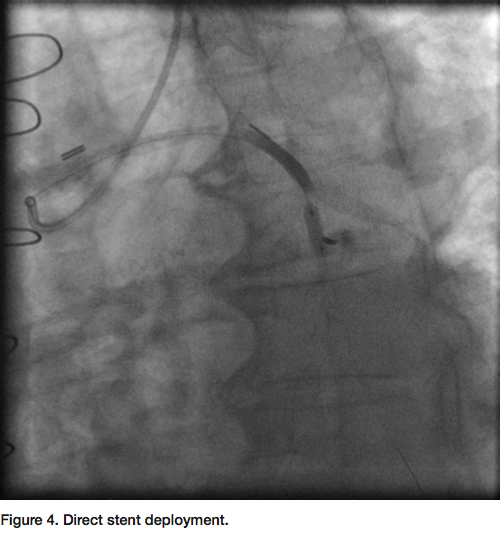

90% eccentric focal stenosis in the distal portion of the vein graft, very close to the anastomosis (Figure 2). Weight-based bivalirudin was initiated and a 6 Fr AL1 guide was used to cannulate the SVG to LAD. Though the severe tortuosity caused the cannulation of the graft to be challenging, a very co-axial supportive guide position was achieved (Figure 3, Figure 5). The lesion was crossed with a Kinetix wire (Boston Scientific). Due to the proximity of the lesion to the anastomosis, no distal protection device was deployed. A 3.5mm x 12mm Resolute drug eluting

stent (DES) (Medtronic) was deployed at high pressure directly to the lesion without pre-dilation (Figure 4). Repeat angiogram confirmed successful deployment of the stent with a TIMI-3 flow and no residual stenosis (Figure 5). The guide and sheath were removed and a hemostatic wrist compression device was applied for 2 hours. The patient tolerated the procedure well. There was no post-procedure increase in the cardiac enzymes and he was discharged home the next day.